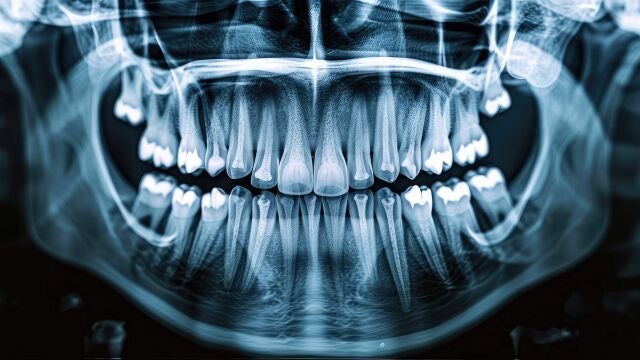

Investigadores de la Universidad Politécnica de Madrid, en colaboración con la spin-off Bioactive Surfaces, han desarrollado una nueva generación de implantes de titanio con moléculas bioactivas, que favorecen su integración en el organismo. Este avance se podrá aplicar en terapias de reemplazo de tejido óseo en trastornos esqueléticos, lo que mejorará su estabilidad y reducirá la respuesta inflamatoria, según los autores.

La reacción del organismo a un implante implica una serie de procesos complejos que limitan severamente su vida útil. Esta limitación no solo afecta la calidad de vida del paciente, sino que también supone una carga significativa para el sistema sanitario.

Para afrontar el reto de desarrollar prótesis más fiables y duraderas, un equipo de investigadores del Centro de Tecnología Biomédica (CTB-UPM) de la Universidad Politécnica de Madrid (UPM), en colaboración con la spin-off Bioactive Surfaces, ha creado una nueva generación de implantes de titanio.

Mediante el proceso R-THAB®, un amplio rango de moléculas con actividad biológica puede adherirse a la superficie del titanio, lo que favorece una mejor integración del implante con el hueso. Estos resultados representan una estrategia prometedora para mejorar la biocompatibilidad de los biomateriales metálicos y avanzar en las terapias de reemplazo de tejido óseo en trastornos esqueléticos.